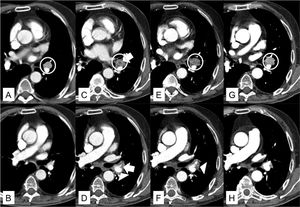

A: TC de tórax en ventana de mediastino a la altura de la bifurcación bronquial. Se identifica una adenopatía patológica e hipercaptante en el hilio izquierdo (circunferencia blanca). B: TC de tórax en ventana de mediastino a la altura de la arteria pulmonar derecha. Arteria lingular permeable. C: TC de tórax en ventana de mediastino a la altura de la bifurcación bronquial, 34 días después de A. Se objetiva la aparición de un foco hipodenso (flecha blanca) en el seno de la adenopatía hiliar izquierda (circunferencia blanca). D: TC de tórax en ventana de mediastino a la altura de la arteria pulmonar derecha, 34 días después de B. Aparición de un trombo agudo de disposición central en la arteria lingular (flecha blanca) y un rodete inflamatorio que engloba las estructuras vasculares del hilio izquierdo (cabeza de flecha blanca). E: TC de tórax en ventana de mediastino a la altura de la bifurcación bronquial, 44 días después de A. La adenopatía hiliar izquierda persiste con mayor aumento de volumen (circunferencia blanca). F: TC de tórax en ventana de mediastino a la altura de la arteria pulmonar derecha, 44 días después de B. Resolución del trombo en el interior de la arteria lingular, pero con persistencia del rodete inflamatorio alrededor de los vasos hiliares izquierdos (cabeza de flecha blanca). G: TC de tórax en ventana de mediastino a la altura de la bifurcación bronquial. Recuperación de las características iniciales de la adenopatía hiliar izquierda, 69 días después de A. H: TC de tórax en ventana de mediastino a la altura de la arteria pulmonar derecha, 69 días después de B. Resolución del rodete inflamatorio que acompañaba a los vasos hiliares izquierdos.

Se trata de un varón de 71 años, diagnosticado 7 años antes de carcinoma renal de células claras en estadio i, que requirió nefrectomía radical izquierda y, 3 años más tarde, segmentectomía atípica en el lóbulo superior derecho por metástasis pulmonar única. Durante el seguimiento de la enfermedad se realizó una tomografía computarizada (TC) de tórax que evidenció una adenopatía interlobar izquierda de 12mm de diámetro menor con necrosis central. La EBUS-TBNA identificó y puncionó una adenopatía interlobar izquierda (estación ganglionar 11L) de 15mm de diámetro menor, cuyo análisis citológico fue compatible con metástasis de carcinoma renal de células claras. Seis días después de la realización de la EBUS-TBNA, el paciente acudió a urgencias por malestar general, fiebre de 38-40°C, disnea y dolor torácico inespecífico. En la analítica sanguínea destacaba una PCR de 16mg/dl y una leucocitosis de 14,96×10^9/l, con una neutrofilia de 13,6×10^9/l. La radiografía de tórax era normal. Se inició tratamiento antibiótico empírico con ceftriaxona y azitromicina, a pesar de lo cual el paciente persistió febril, por lo que se decidió solicitar una TC de tórax, que confirmó la persistencia de la adenopatía interlobar izquierda que estaba rodeada de una imagen de densidad de partes blandas adyacente a la adenopatía, especialmente en su margen superior, que era el del potencial recorrido de la aguja y también englobaba la arteria lobar inferior izquierda, así como una imagen de trombo agudo en la emergencia de la rama lingular de la arteria pulmonar (fig. 1). Con el diagnóstico de adenitis intrapulmonar con trombosis arterial asociada se cambió la cobertura antibiótica a piperacilina/tazobactam y linezolid y se inició tratamiento anticoagulante con enoxaparina 1mg/kg de peso cada 12h. La evolución del paciente fue favorable, con resolución de la fiebre y normalización de los parámetros inflamatorios. Una TC de tórax un mes después del alta mostraba la resolución de la adenitis intrapulmonar y de la trombosis de la arteria lingular.